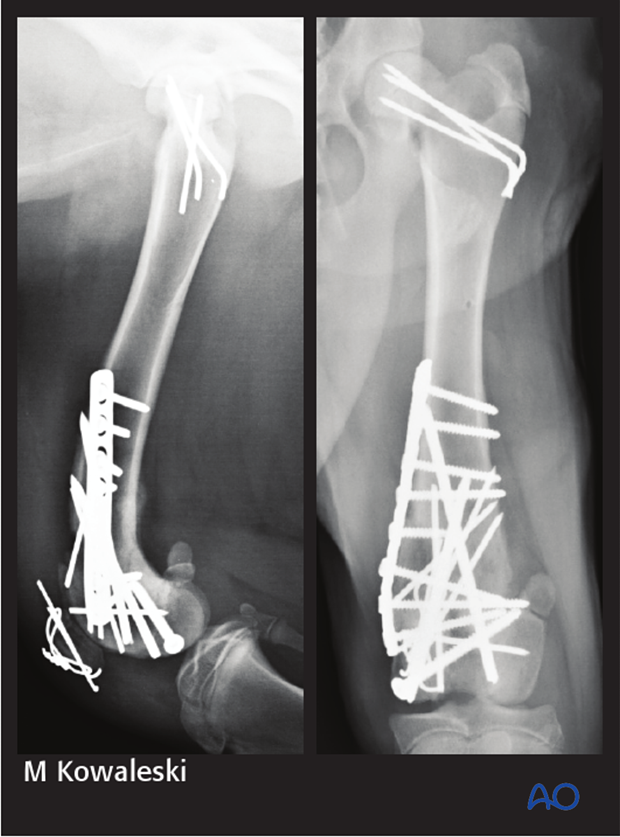

4-week postoperative radiographs demonstrate stable implants and progressive healing. The patient was clinically doing very well. The implants were not removed.